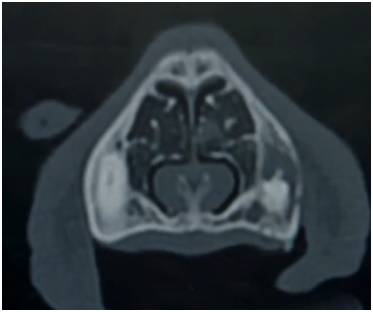

狗狗鼻腔内有呈涡旋状的

鼻甲骨

,上面被覆有嗅上皮细胞,汪星人鼻腔内的这种涡旋状结构展开可以达90平方厘米,有约1.5亿个嗅觉受体,不同品种会有差异,比如腊肠犬有1.25亿个嗅觉受体,寻血猎犬有3亿个嗅觉受体!